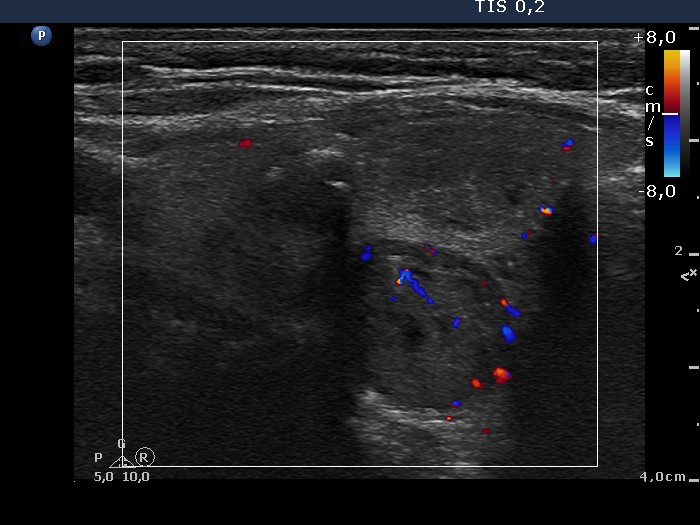

First examination (1st and 2nd rows of images)

Ultrasonography: the right thyroid contained three nodules, the two ventral lesions were minimally-moderately hypoechogenic, while the dorsal one was hypoechogenic. The latter presented a combined type 2 and type 3 vascular pattern.

Cytology was performed from the dorsal, hypoechogenic nodule and resulted in benign, follicular proliferation. The risk of a carcinoma was estimated to be less than 1%.